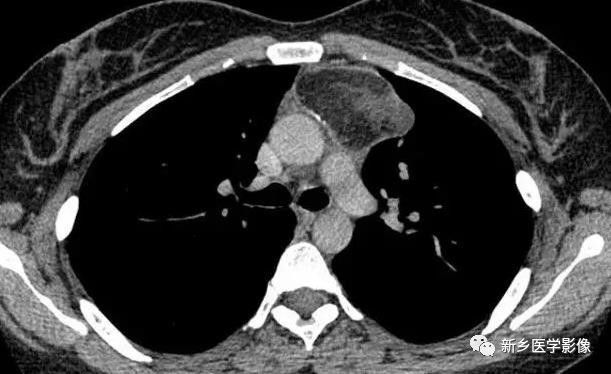

2.CT表现:非侵袭性胸腺瘤CT平扫示前纵隔内类圆形软组织肿块,多数密度均匀。增强后均匀强化,囊变的部分呈低密度且无强化表现。侵袭性胸腺瘤肿块常较大,密度不均匀,包膜不完整,周围脂肪组织层消失,侵犯邻近的胸膜、心包膜等结构,并可伴胸腔积液。

非侵袭性胸腺瘤CT图像

a. CT平扫示前上纵膈主动脉弓与胸骨间软组织密度肿块,密度均匀,边缘浅分叶状 b. CT增强示肿块均匀强化,肿块与主动脉弓之间脂肪间隙清晰

侵袭性胸腺瘤CT图像

a. CT平扫示肺动脉与胸骨间肿块,密度尚均匀,形态不规则b. CT增强示肿块不均匀强化,见低密度囊变区域,肿块与肺动脉之间脂肪间隙消失,肺动脉壁模糊。